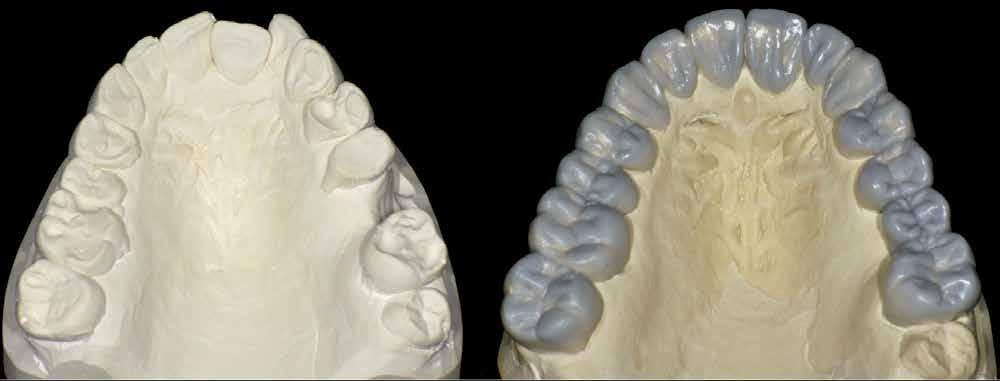

A laboratóriumban szekciós minta készült, blokk-stiftekkel (1. kép) , amelynek készítése során nagy figyelmet szenteltünk az ínymaszk (Majesthetik- Gingiimplant picodent) és a felfekvő lengőtag területének (2–6. képek)

A minta beolvasása után számítógéppel terveztük meg a híd vázát (7. kép). 0,06 mm-es cementrést terveztünk a teljes karfelület alá, 1 mmre végződve a preparáció szélétől (8–11. képek)

Így egyenlítettük ki a kötésjavító vastagságát, sikeresen. Az adatokat elküldtük az AHRtec-frézközpontba, néhány nap múlva visszakaptuk a cirkonvázat (12. kép). A marási paraméterek optimális betartása következtében a passzítás egyszerű volt (13. kép)